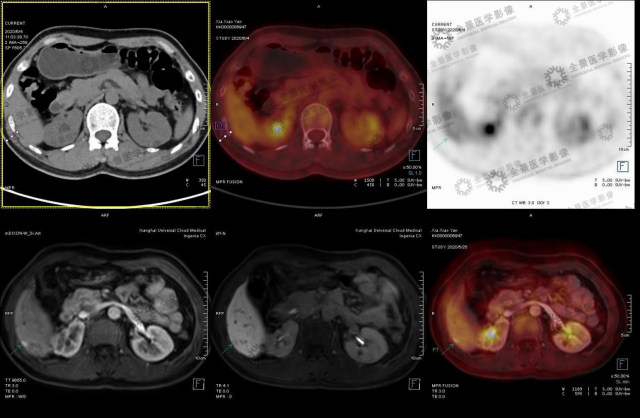

中年女性 外院体检发现肝脏小结节,乙肝病史不详。无明显不适症状。2020.5 于本中心行腹部 MRI 示:肝右后叶下段包膜下小结节,考虑小肝癌可能。

肝右后叶下段包膜下小结节,考虑小肝癌